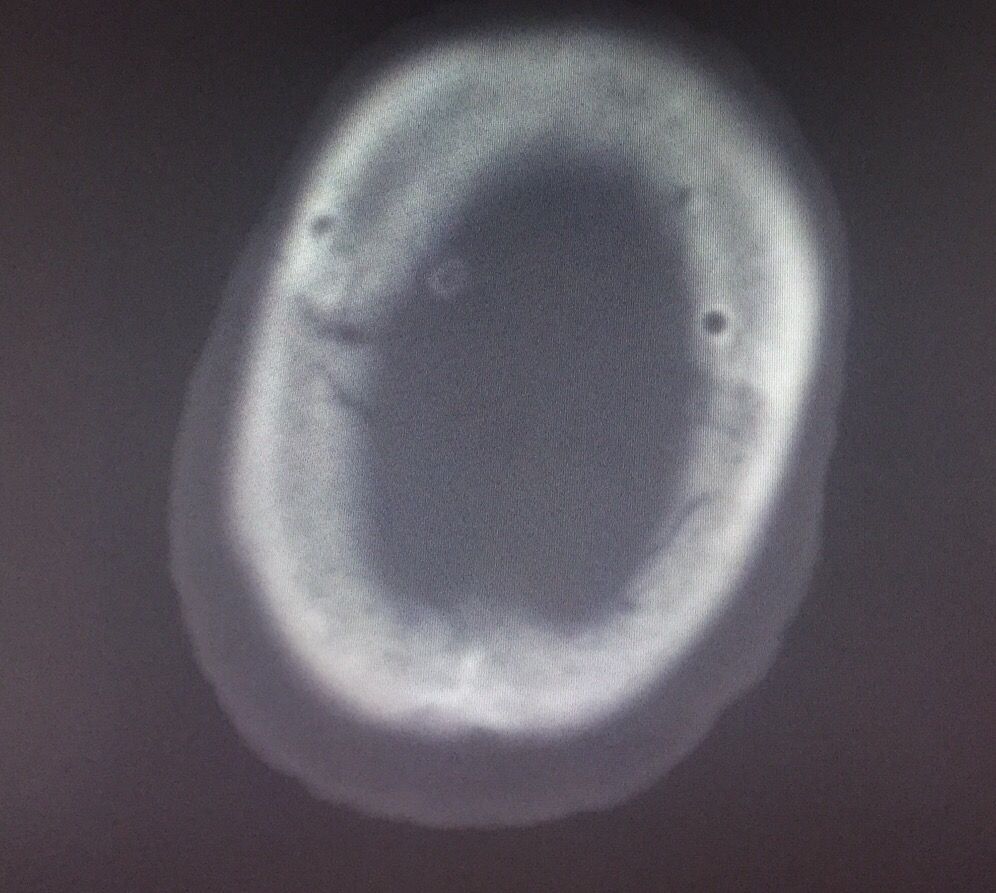

Kocher点的验证↓↓↓

从最后复查的骨窗位可以看到钻孔的位置

定位还算准确

脑窗还可以看到穿刺管的路径↑